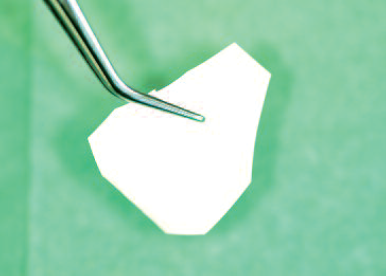

Collagen membrane cut to the defect size